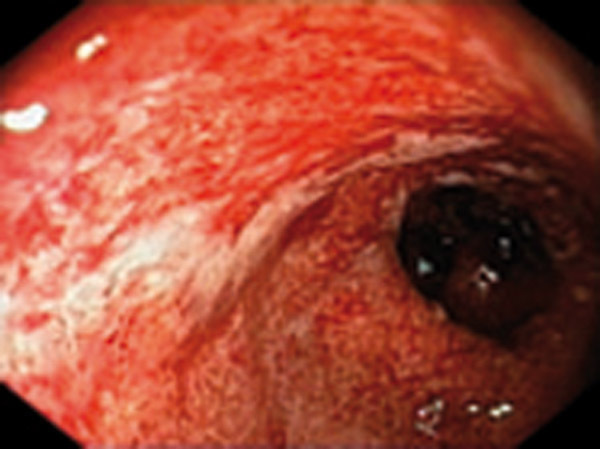

Rectocolite hémorragique de score 3

Rectocolite sévère : saignement spontané, ulcérations